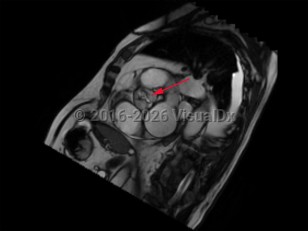

Hypertrophic cardiomyopathyHypertrophic cardiomyopathy

Congestive heart failureCongestive heart failure

Coronary artery disease